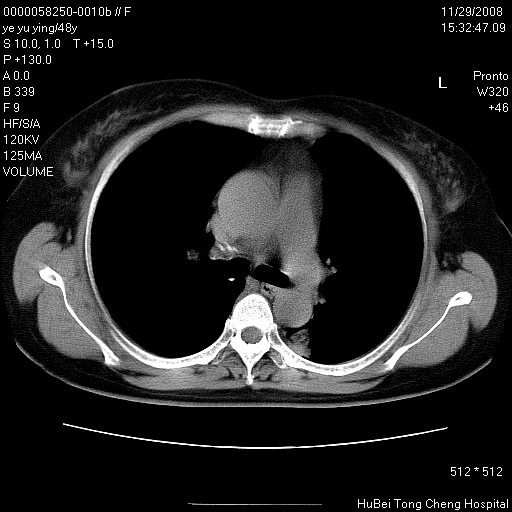

以下是引用zsl6918在2008-11-29 21:47:00的发言:[br]恶性肿瘤病史,转移瘤首先考虑。脂肪肝,胆囊结石。

以下是引用huenhao在2008-11-29 22:11:00的发言:[br]脂肪肝,胆囊结石。左肺病灶建议定期复查。

以下是引用liuyue在2008-11-30 5:44:00的发言:[br]1.左肺病变,首先考虑感染性病变,转移待排;建议治疗后复查。[br]2.肝脏密度普遍减低,考虑与化疗有关。[br]3.胆囊结石.